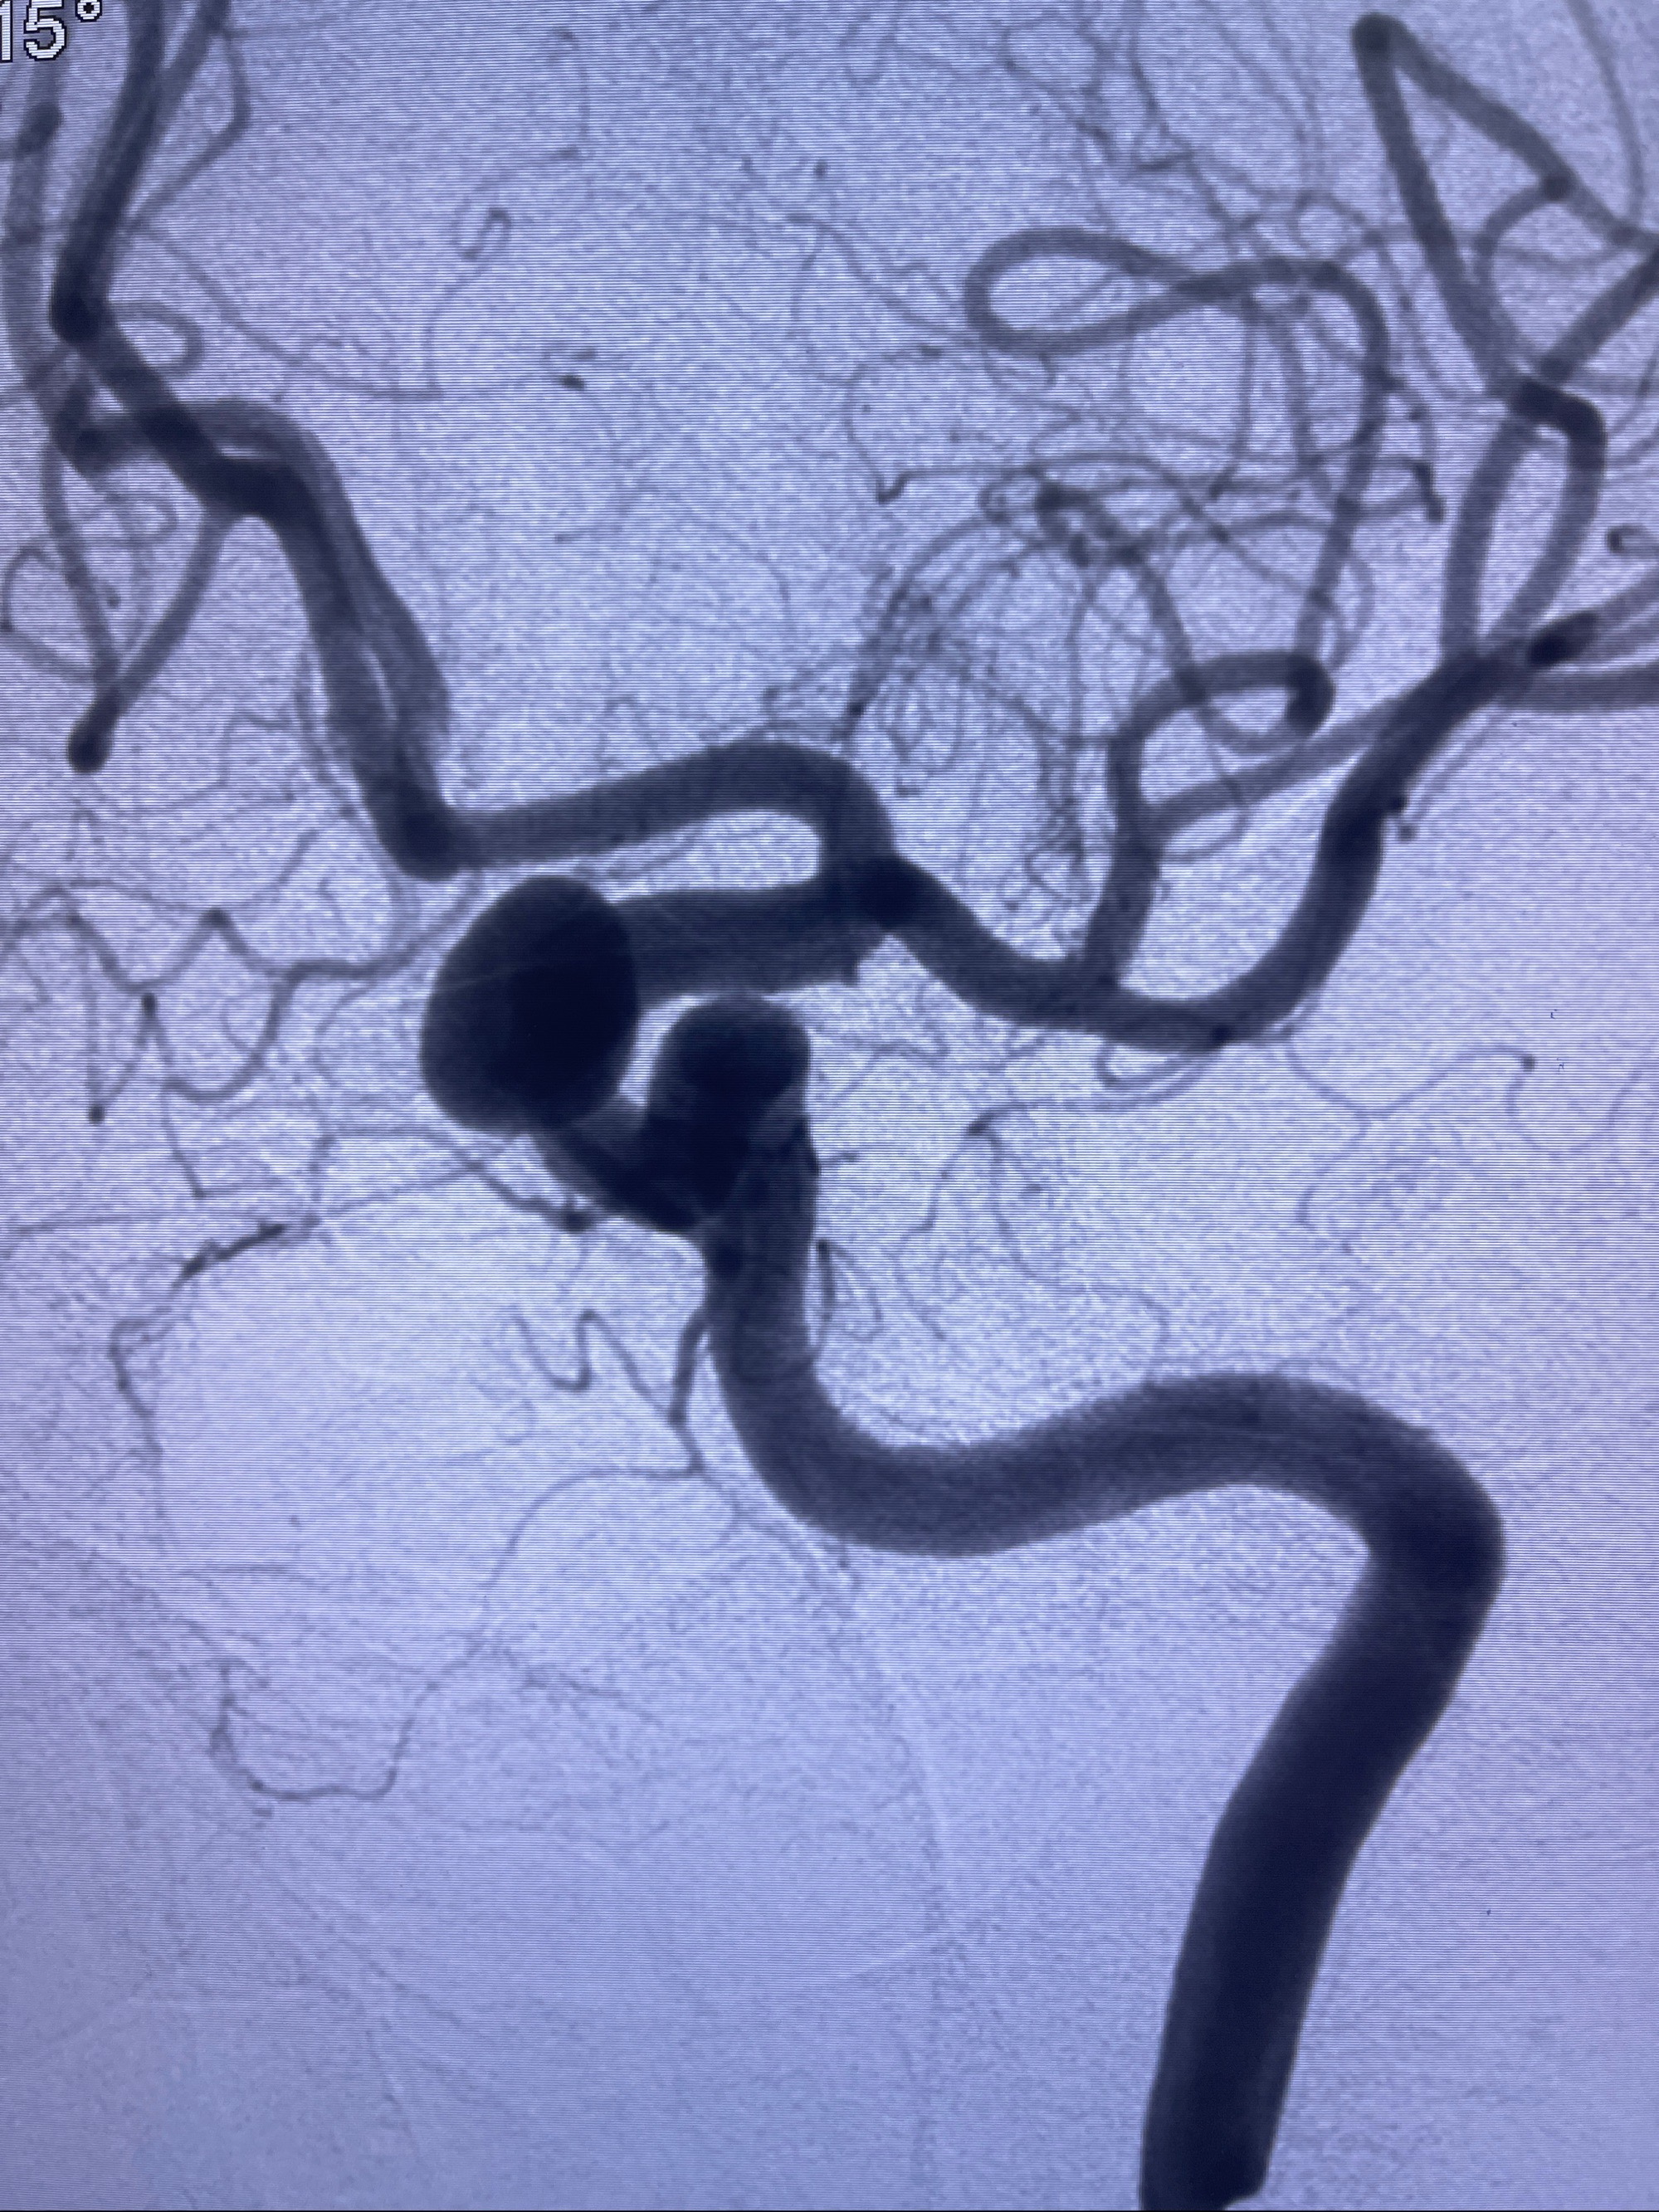

2023-08-30DSA:左侧颈内动脉眼动脉动脉瘤,约3*9.2*7.3mm大小

2023-09-06全麻下行左侧颈眼动脉瘤

密网支架辅助栓塞